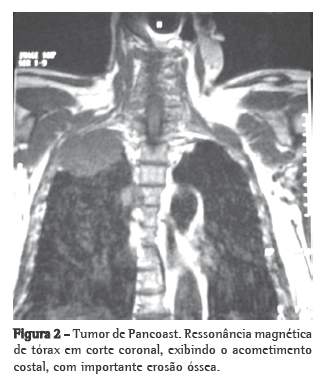

Homem branco de 74 anos, pintor, hipertenso, com insuficiência vascular periférica de membros inferiores, tabagista durante 54 anos (uma carteira de cigarros por dia). Há dois meses iniciou quadro de dor em hemitórax direito, ventilatório-dependente, tipo pontada, associada à tosse produtiva serosa e dispneia aos grandes esforços. Ao exame físico na internação mostrava apenas redução universal do murmúrio vesicular, além de redução dos pulsos pediosos, sem déficits neurológicos. Não apresentava alterações no hemograma, nos testes bioquímicos do sangue e no exame urinário. Seu PPD foi não-reator e a pesquisa de bacilos álcool-ácido resistentes no escarro foi negativa. Exames de imagem do tórax (Figuras 1 e 2) evidenciavam massa de limites regulares no sulco superior direito do tórax, com acometimento de vértebras e costelas adjacentes. A cintilografia de corpo inteiro com gálio e a tomografia de crânio foram normais. Foi submetido a uma punção e biópsia transtorácica, cujo estudo histopatológico mostrou tratar-se de um carcinoma de pequenas células de pulmão (Figura 3). Evoluiu durante a internação com parestesia em região axilar direita e piora da dor torácica, agora mais intensa sobre a escápula direita. Mesmo apresentando doença localmente avançada, devido às comorbidades, foi submetido apenas ao tratamento radioterápico, com dose única de 50 Gy.

Foi iniciada uma investigação da massa pulmonar, com tomografia e ressonância magnética de tórax. Mesmo com a evolução das técnicas em aquisição de imagens em tomografia computadorizada, com melhor abordagem na detecção e avaliação do crescimento tumoral, bem como na extensão da infiltração da parede torácica e envolvimento mediastinal,(9) a ressonância magnética de tórax continua sendo o melhor exame para a avaliação dos tumores do sulco superior.(10-12) A ressonância magnética de tórax fornece as mesmas informações da tomografia, com incremento na avaliação do acometimento do sistema nervoso central.(10)